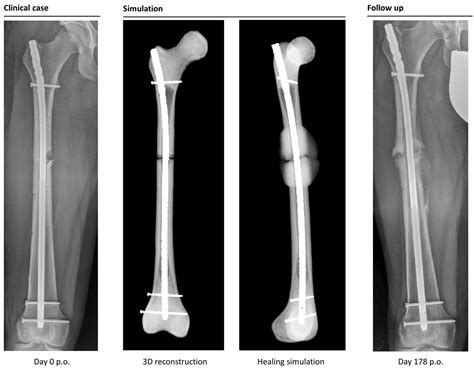

Following the surgical repair—typically involving intramedullary nailing, plates, or screws—the first few weeks are focused on stabilization and pain management. During this time, the body initiates the "inflammatory phase" of healing, where blood clots form and the body begins to clear away damaged tissue. It is critical to follow the surgeon’s weight-bearing restrictions strictly, as putting pressure on the leg too soon can displace hardware or interfere with bone union.

Broken femur recovery is not linear; it moves through several distinct phases. While every patient’s biology is different, the general timeline follows a predictable pattern of physiological repair. This table provides a high-level overview of what to expect during the first six months.

Returning to your pre-injury lifestyle is a marathon, not a sprint. The success of your broken femur recovery relies heavily on your commitment to physical therapy, your patience with the slow pace of bone remodeling, and your ability to maintain a positive mental outlook. By focusing on consistent, low-impact exercise and proper nutrition, you create the optimal environment for your femur to regain its strength and functionality. Always listen to your body and work closely with your healthcare providers to navigate the challenges of each stage, ensuring that you build a solid foundation for a full return to your daily activities. While the path may be long, steady progress eventually leads to restored independence and a return to the life you enjoyed before the injury.